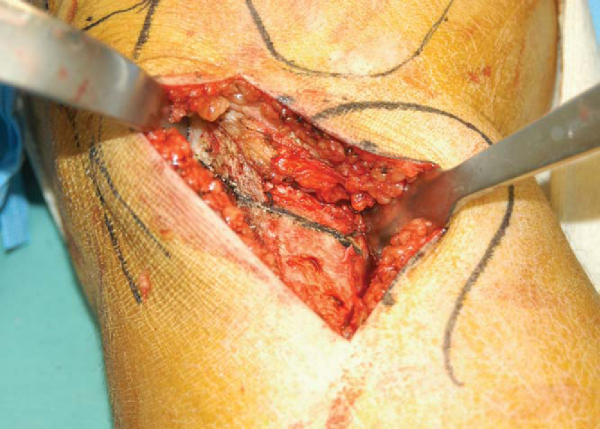

A 6-cm incision is made 1 cm distal to the joint line and halfway between the tibial tuberosity and the posteromedial border of the tibia. The subcutaneous tissue is dissected sharply down to the level of the sartorius fascia. Starting at the medial edge of the tibial tubercle, the sartorius fascia is incised longitudinally. The sartorius fascia and the pes anserine are then elevated off the medial tibia to the level of the medial collateral ligament. The deep fibers of the medial collateral ligament are then raised from an anterolateral to posteromedial direction subperiosteally. A Homan retractor is then placed around the posteromedial corner of the tibia. The medial edge of the patellar tendon is then identified, and a longitudinal incision just medial to the tendon is made for a short distance in a superior direction. This allows placement of a second Homan retractor just superior to the tibial tuberosity and underneath the patellar tendon, thereby protecting it during the osteotomy cuts (

Fig. 58-2

). The medial proximal tibia is thus exposed. Two parallel guide pins are placed just proximal to the intended osteotomy line. The starting point for these pins is approximately 3 to 4 cm distal to the medial joint line. The pins are directed in an oblique fashion from an inferior-medial position to a superior-lateral position (Figs. 58-3 and 58-4 [3] [4]). Because the proximal tibia is sloped posteriorly, the osteotomy must be made in an oblique fashion to maintain an adequate bridge of bone along the posterior cortex of the tibia. The pins should be no less than 1 cm from the joint surface of the lateral tibial plateau. The pins guard against proximal migration of the osteotomy toward the joint. Distances less than 1 cm are more likely to fracture into the joint at the time of osteotomy correction. Absolute requirements for pin placement include osteotomy placed above the insertion of the patellar tendon, adequate distal starting point to allow proximal plate fixation, and osteotomy at least 1 cm distal to lateral tibial articular surface. A small sagittal saw is then used from anterior to posterior to initiate the osteotomy cut just below the two guide pins and parallel to them. Thin broad AO osteotomes are then used to complete the osteotomy. The use of thicker, more traditional osteotomes can lead to fracture into the joint. Fluoroscopic images are obtained throughout to ensure that the lateral tibial cortex is not violated and to ensure parallelism between the guide pins and the osteotome (Figs. 58-5 and 58-6 [5] [6]).